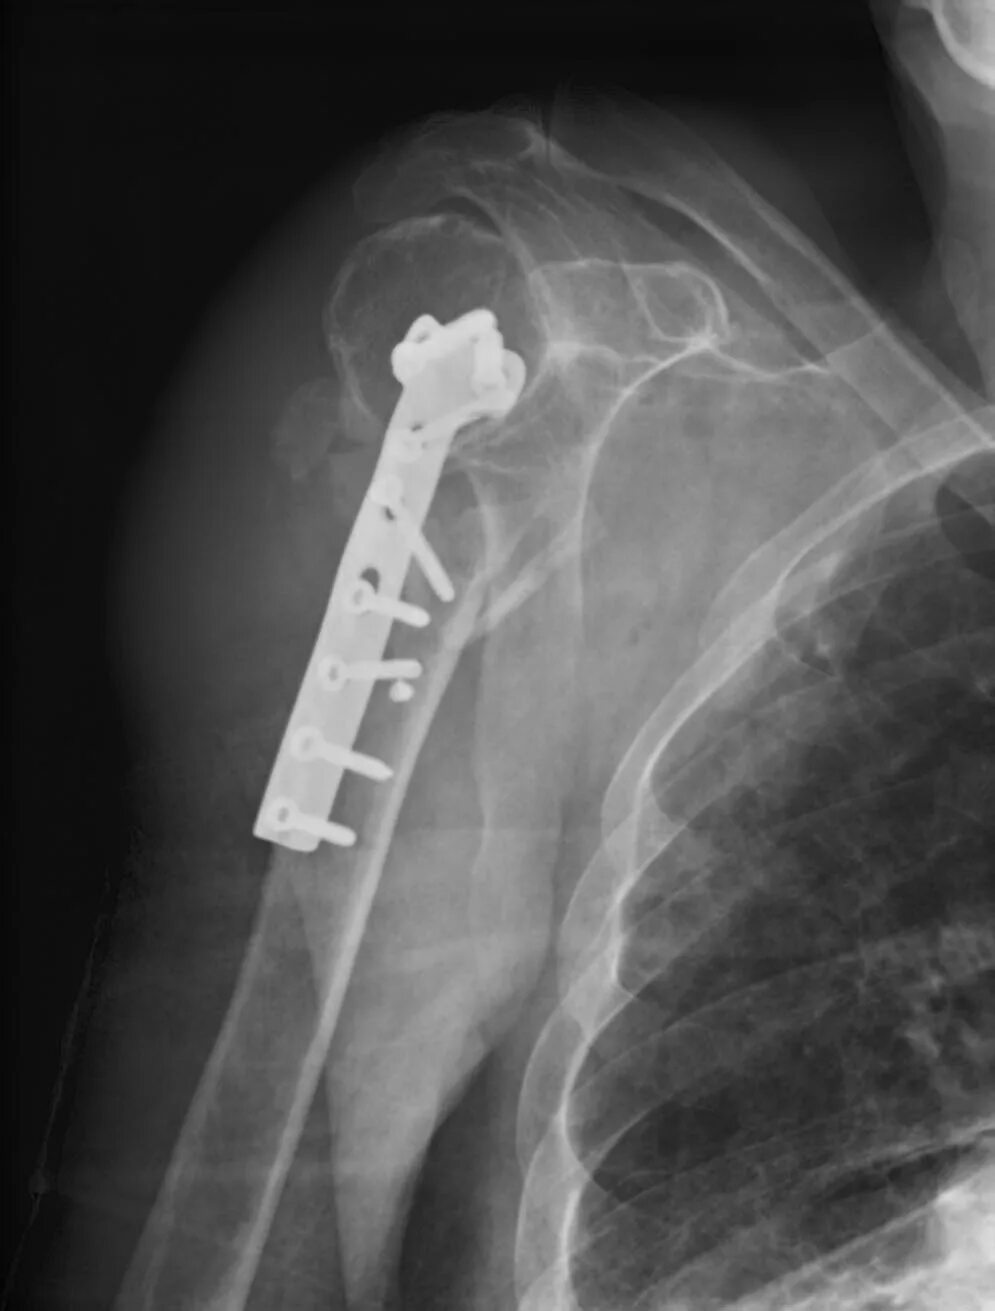

Перелом шейки плеча у пожилых